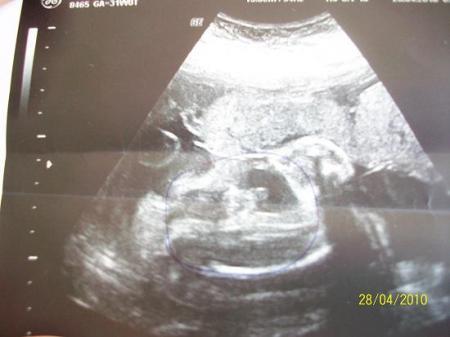

Lach, ja so ist das. Wie bei uns . Mein US-Bild sieht fast genauso aus.